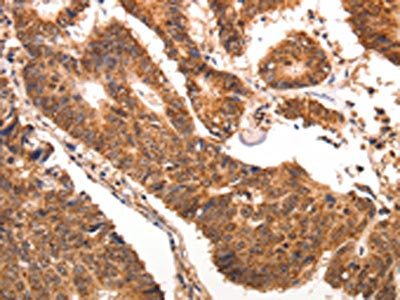

The image is immunohistochemistry of paraffin-embedded human colon cancer tissue using CSB-PA113746(CCL17 Antibody) at dilution 1/70. (Original magnification: ×200)

The image is immunohistochemistry of paraffin-embedded human gastric cancer tissue using CSB-PA113746(CCL17 Antibody) at dilution 1/70. (Original magnification: ×200)